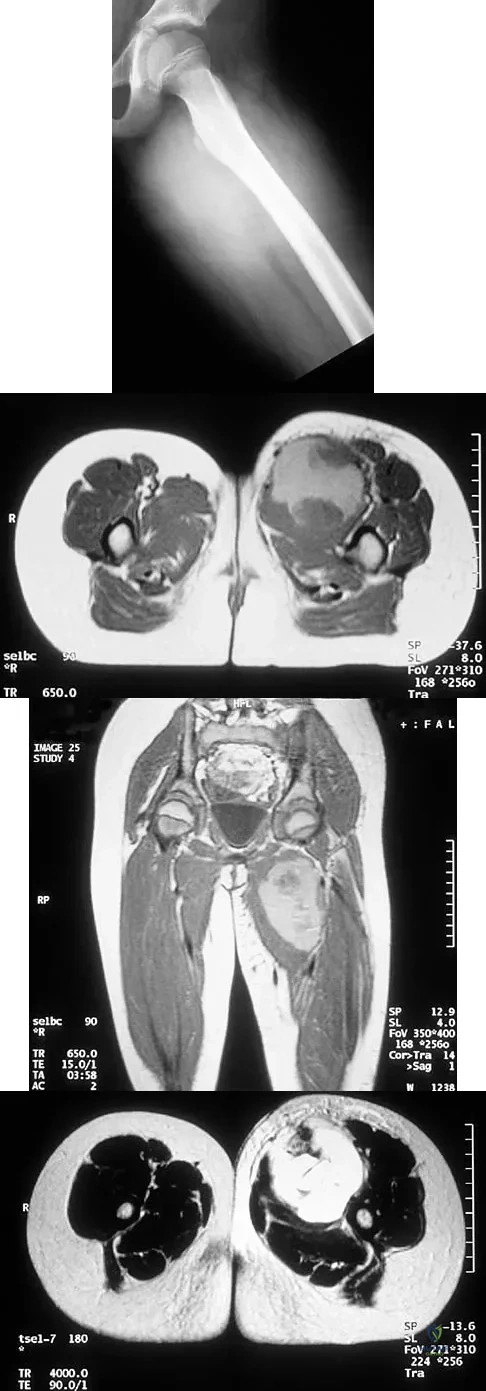

An 8-year-old girl has had a painless enlarging mass of insidious onset in the left thigh for the past 3 weeks. Her mother denies any history of trauma, fever, or disease. Examination reveals a nontender, mobile mass in the left medial thigh. Her gait is normal. Figures 25a through 25d show the frog-lateral radiograph, the axial and coronal T1-weighted MRI scans, and the axial T2-weighted MRI scan. Biopsy results reveal a nonrhabdomyosarcoma soft-tissue sarcoma. The most appropriate treatment should consist of